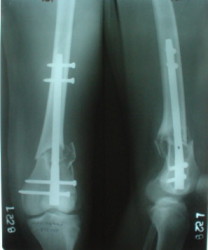

1

2

The mobilisation of knee is started immediately from the second day. Weight bearing is permitted as in any other interlocked nailing. That is, Toe touch to start with and within four days, partial to in another two weeks, full weight bearing. Of course that is assuming that the correct size nail has been used. Up to 70 kg body weight, 11no will be good enough and 12mm if more.Usually at the 1st followup, at 6 weeks time, they have full flexion..I

have seen a few surgeons putting in a drain, but I have not found it unnecessary. There has never been any effusion needing active treatment.

Enclosing a recent intraop picture